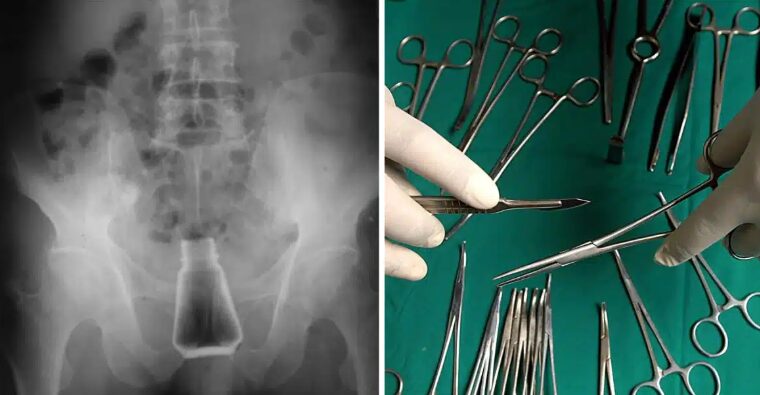

Ο ασθενής μεταφέρθηκε εσπευσμένα στο νοσοκομείο της Σύρου, καθώς κινδύνευε η ζωή του…

Οι πληροφορίες του logotypos αναφέρουν ότι ο εν λόγω άνδρας είχε για δύο ολόκληρες ημέρες στον πρωκτό του το μπουκάλι με το αλάτι, καθώς ντρεπόταν να πάει σε γιατρό. Όπως αντιλαμβάνεστε, υπήρχαν φόβοι να πάθει σηψαιμία.

Αμέσως, ο ασθενής μπήκε στο χειρουργείο και του αφαιρέθηκε το αντικείμενο που υπήρχε στον πρωκτό του, προτού υπάρξουν πιο δυσάρεστες συνέπειες για την υγεία του.

Μάλιστα, σε ερώτηση του γιατρού του νοσοκομείου Σύρου, για το πώς βρέθηκε το μπουκάλι με το αλάτι στον πρωκτό του. Ο άνδρας υποστήριξε ότι ήταν ένα ατύχημα, καθώς έπεσε από σκάλα και προσγειώθηκε πάνω στο αλάτι.